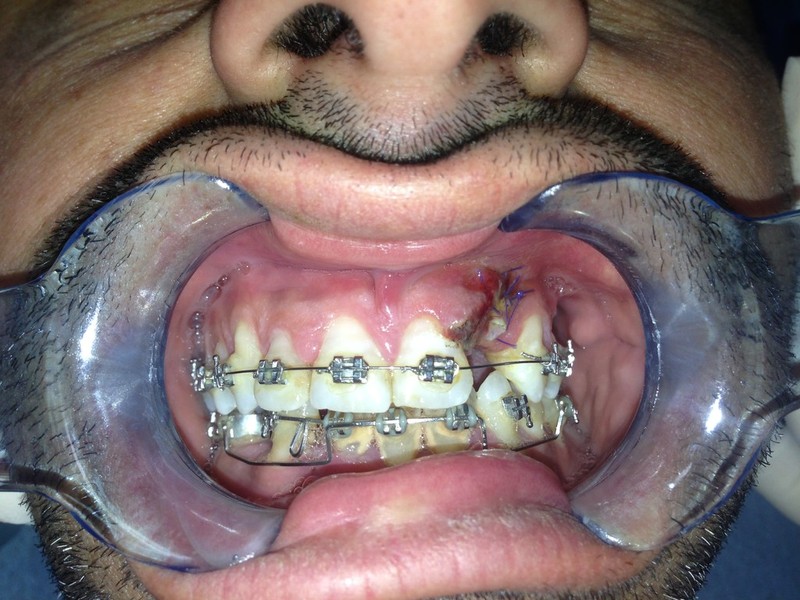

Chirurgia plastica Muco-Gengivale

Rigenerazione Gravi difetti parodontali

rigenerazione grave difetto parodontale a carico una intera emiarcata